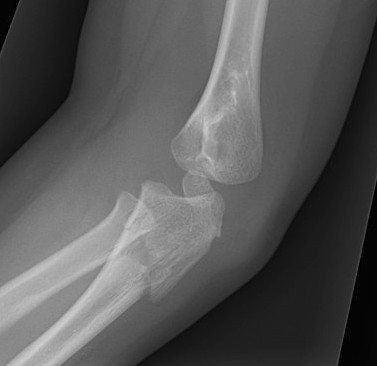

Case 1. Missed Monteggia, injury 6 months ago